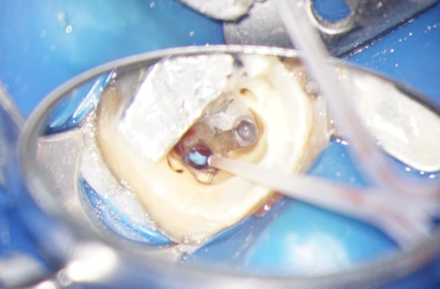

După îndepărtarea unui segment din pivot, vedem cavitatea artificială care traversează grosimea dintelui, până în țesutul de susținere (Fig. 4.12.8). În țesutul de susținere se observă un material albastru, gumos. Este cel mai probabil un material din clasa silicaților, folosit pentru amprentarea spațiului din interiorul dintelui pentru confecționarea pivotului metalic (Fig. 4.12.9). Reușim să îndepărtăm o parte a acestui material și închidem perforația folosind un ciment bioceramic (MTA) (Fig.4.12.10, Fig. 4.12.11).